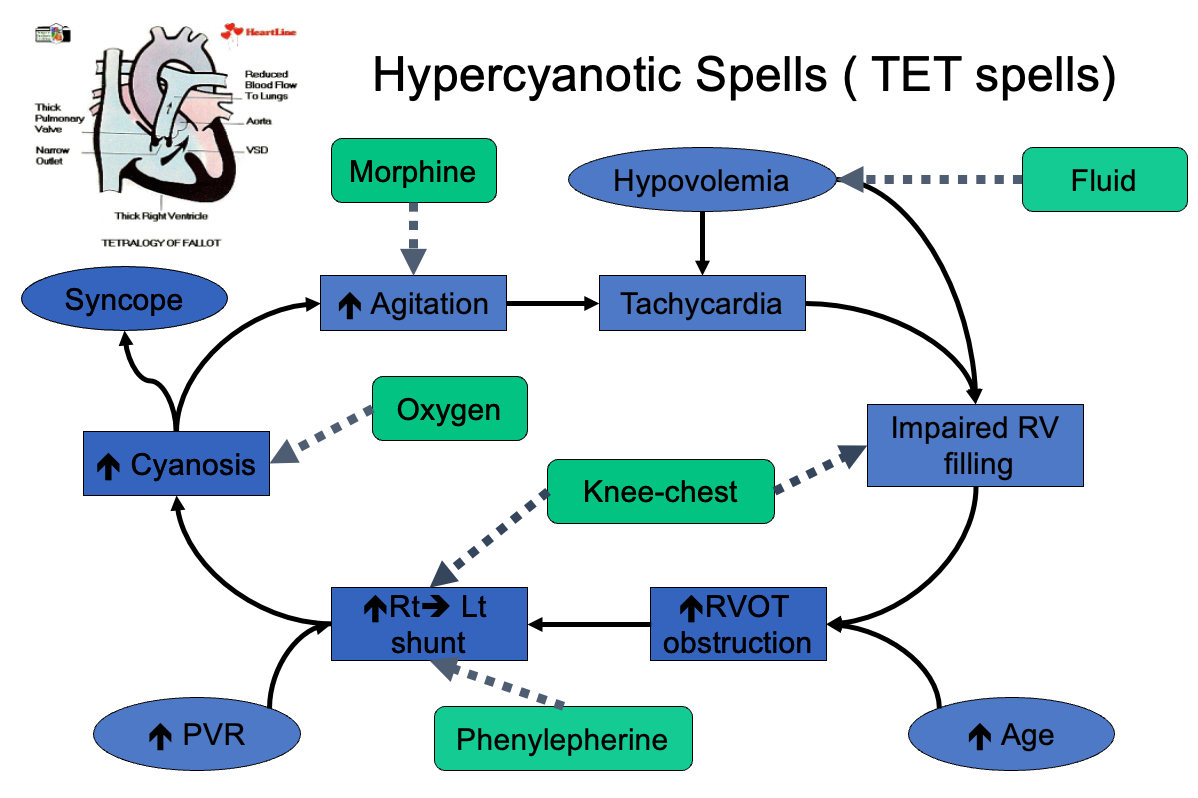

Hypoxic (Tet) spells: - Hyperpnea occurs with gradually increasing cyanosis and loss of the murmur. - Prolonged unconsciousness and convulsions, - hemiparesis, or death may occur.

Treatment of Tet Spell

-

Quiet, calm environment

-

Knee-chest or squatting position increases afterload thus increasing systemic resistance

-

Oxygen

-

Morphine to reduce spasm and/or sympathetic stimulation

-

Phenylephrine increases afterload by promoting systemic vasoconstriction

-

Crystalloids: consider small volume challenge (5-10 cc/kg) to increase preload and SVR

-

NaHCO3 to treat acidosis

Tachycardia

- Impaired RV filling

- Increased RVOT obstruction

- Increased Rt→Lt shunt

- Increased Agitation

- Hypovolemia

- Increased Age

- Increased PVR

- Hypercyanotic Spells (TET spells)

- Increased Cyanosis

- Syncope

- Fluid

- Morphine

- Oxygen

- Phenylephrine

- Knee-chest

Cyanotic Spells

-

Increase systemic vascular resistance

- Squat/Knee chest position

- Ketamine 1-2mg/kg IV

- Neosynephrine 0.02mg/kg IV

-

Tachycardia & Release of infundibular spasm

- Propranolol 0.1mg/kg IV

-

Irritability: Morphine 0.2mg/kg S.C or IM

-

Hypoxia: Oxygen

-

Dehydration: Volume

-

Acidosis: NaHCO3 1mEq/kg IV